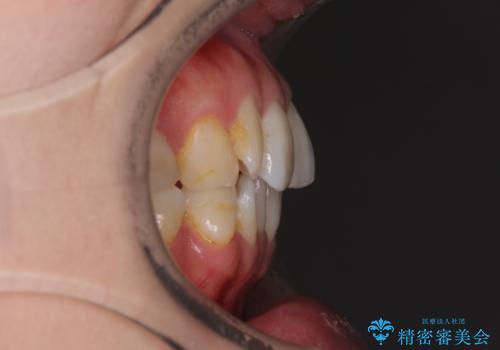

- 失活により変色した歯と不揃いな口元を気にして来院された患者様です。

口元をインビザラインにより歯列を整え、その後に失活している奥歯をオールセラミッククラウンにて補綴治療することとしました。

長時間のマウスピース装着と、患者様自身でのゴムかけに協力いただき、自然な口元に仕上げることができました。

気になっていた変色した歯もオールセラミッククラウンで本物の歯のようになり、患者様には大変満足していただきました。